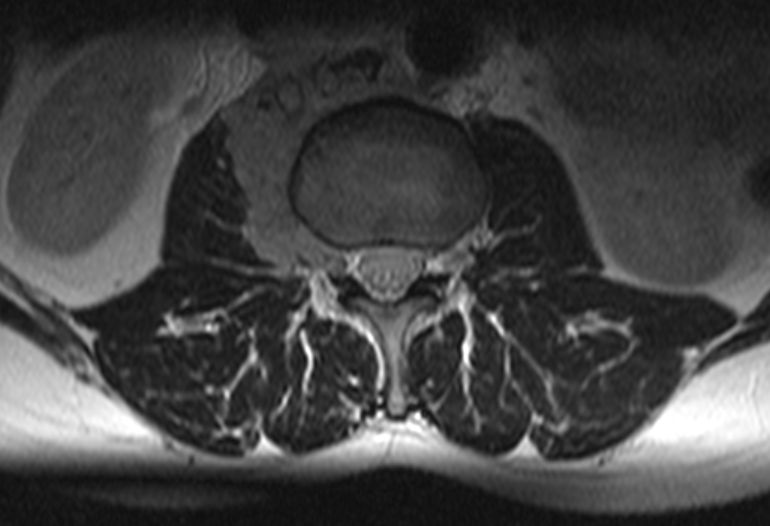

Rezidiv 1 Jahr nach follikulärem Lymphom

MRT